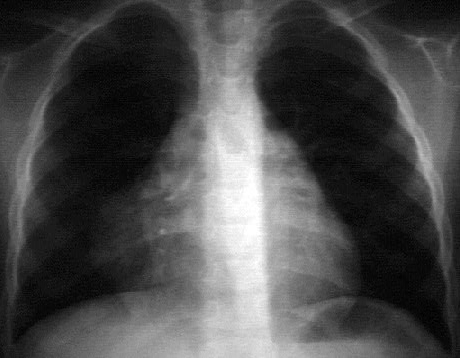

This chest X ray demonstrates a pericardial cyst. This PA view shows apparent prominence of the right heart border. Careful inspection shows a smooth, round, soft tissue density distinct from and adjacent to the right heart border. The typical appearance of a benign pericardial cyst.